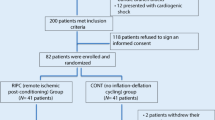

Between June 2008 and October 2010, 76 patients diagnosed with STEMI met the inclusion criteria and were considered eligible for the study. The study patient population is described in Fig. 1.